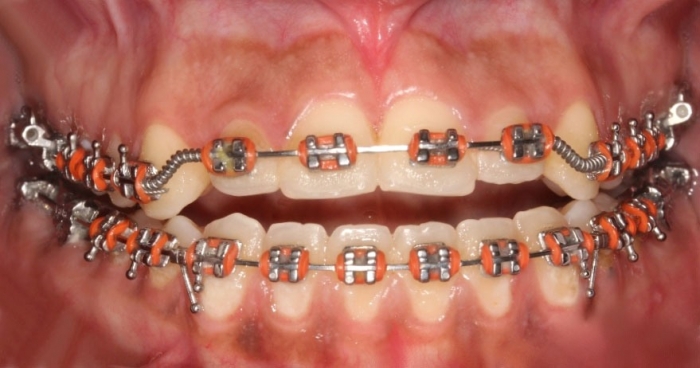

Mordida Inicial - Clínica Cliniface

Mordida Inicial

Mordida após a cirurgia  - Clínica Cliniface

Mordida após a cirurgia